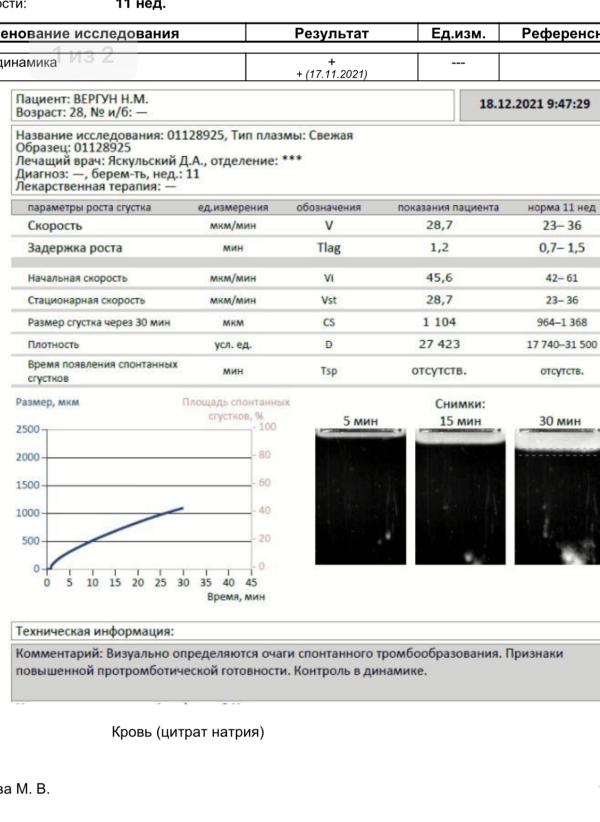

Была у гематолога (Яскульский) 4.12 и на тот момент тромбодинамика и коагулограмма были в полном порядке.

У меня есть мутации по свёртываемости,в первую беременность сначала принимала разные лекарства типа Курантил,Вессел Дуе Ф,Детралекс и т.д.,с 32 недели начала колоть Гемапаксан.

Сейчас пока врач сказал только контроль анализов раз в месяц.

Сдаю сегодня тромбодинамику и как-то вот совсем не радует заключение( К гематологу зап...